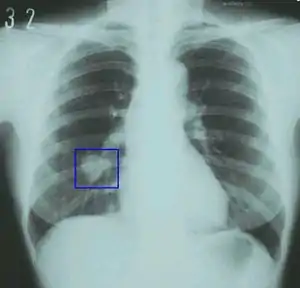

- cancer of the lung (most cases), and some cancers of the bladder, blood (acute myeloid leukemia), cervix, colon and rectum, esophagus, kidney and ureter, larynx, liver, oropharynx, pancreas, and stomach